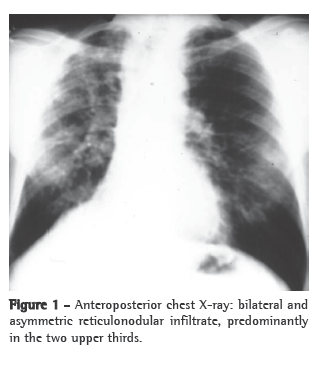

A simple chest X-ray (Figure 1) can reveal asymmetric reticulonodular infiltrate, predominantly in the two upper thirds of both lungs, accompanied by hypertransparent areas at the lung bases.(1,2,4)